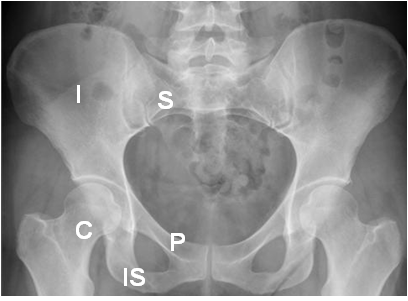

Fig 9. Estructuras óseas en la pelvis.

Rx AP. I: Iliaco. IS: Isquion. P: Pubis. S: Alerón del sacro. C: Cabeza femoral.